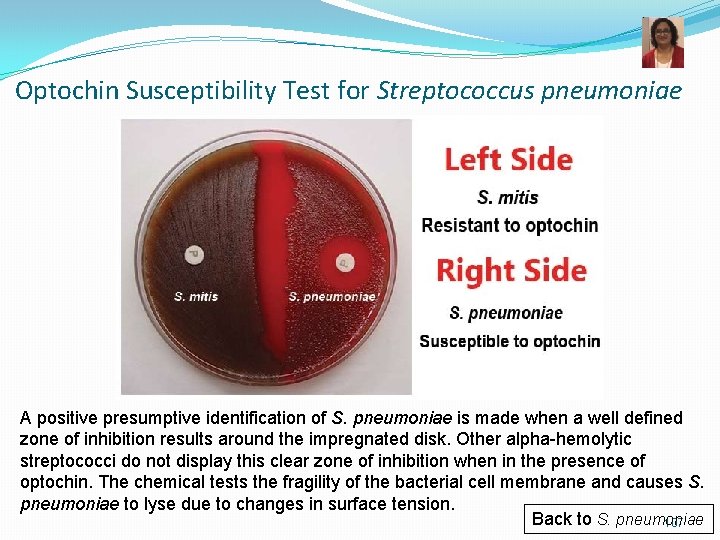

Optochin Susceptibility Test for Streptococcus pneumoniae A positive presumptive identification of S. pneumoniae is made when a well defined zone of inhibition results around the impregnated disk. Other alpha-hemolytic streptococci do not display this clear zone of inhibition when in the presence of optochin. The chemical tests the fragility of the bacterial cell membrane and causes S. pneumoniae to lyse due to changes in surface tension. Back to S. pneumoniae 107